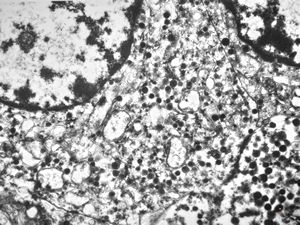

M,2y. | normal hepatocyte